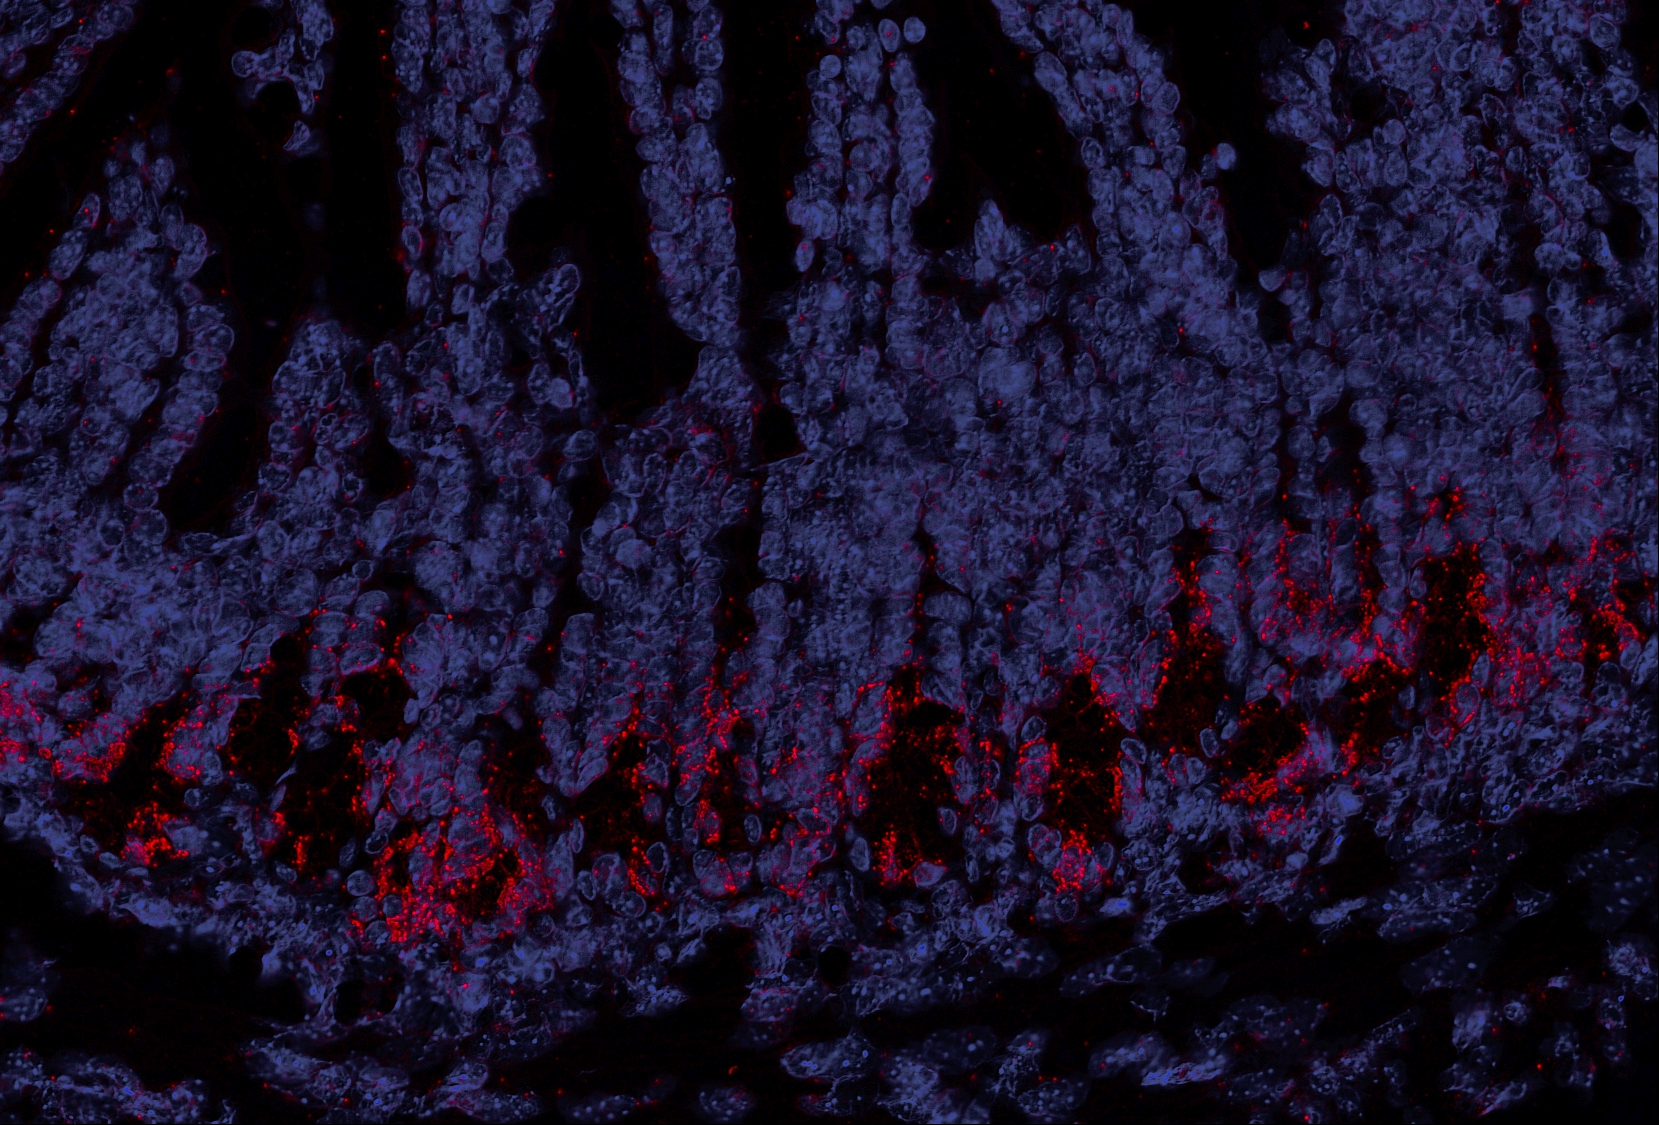

Schnittbild eines Mäusedarms: OLFM4-Stammzellen (rot) sind wichtig für die Regeneration des Epithels.

Während der Behandlung im Vorfeld einer Stammzelltransplantation werden sie oft zerstört. Poeck / TUM